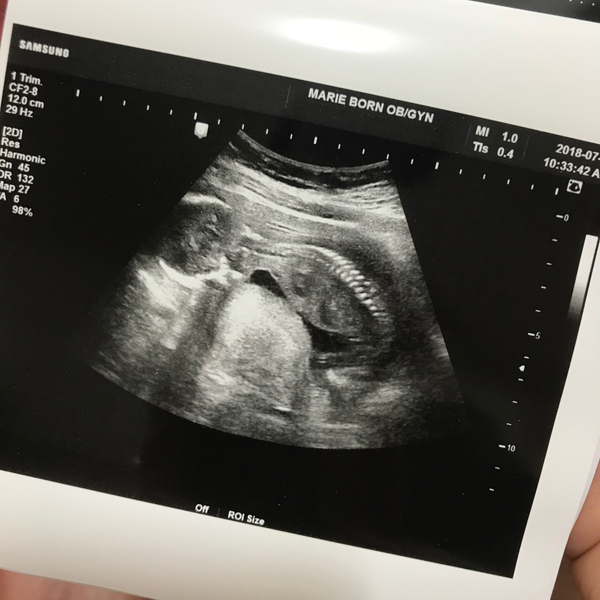

[⚝별하이야기/임신17주-임신21주]한달만에 정기검진/정밀초음파

한달만에 So~ Hi!! 정신없이 살림과 밍기적을 반복하니 벌써 한달이 지나갔다!! 배가 이젠 제법 나와서 ...